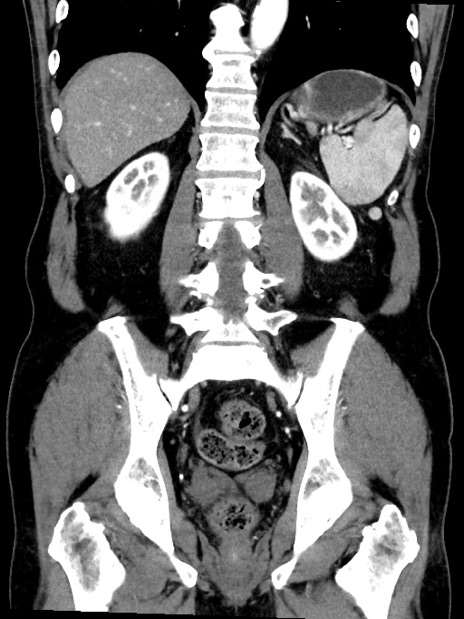

症例35(冠状断像)

【症例】70歳代 男性

【主訴】腹部膨満、嘔吐

【現病歴】昨日より腹部膨満感出現。本日増悪し、仙痛出現。嘔吐あり、受診。

【既往歴】糖尿病、胆摘後

【身体所見】BP 149/80mmHg、HR 74/min、BT 35.9℃、腹部:膨満、軟、圧痛なし。腸雑音減弱あり。上腹部正中切開瘢痕あり。

【データ】WBC 13500、CRP 1.72